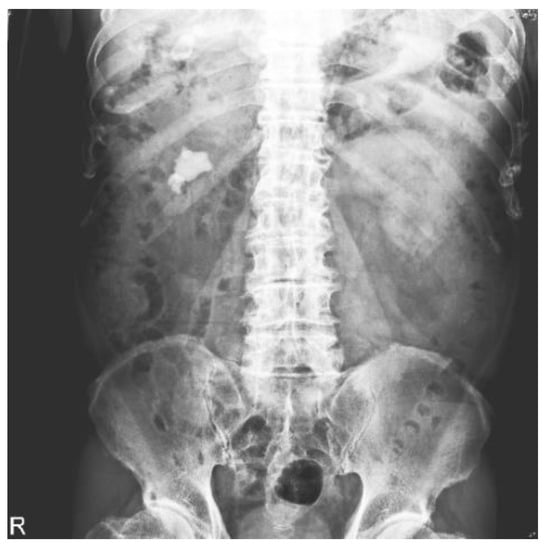

2.2. Datasets

2.3. Image Preprocessing

2.3.2. Image Mask

2.3.3. Image Cropping